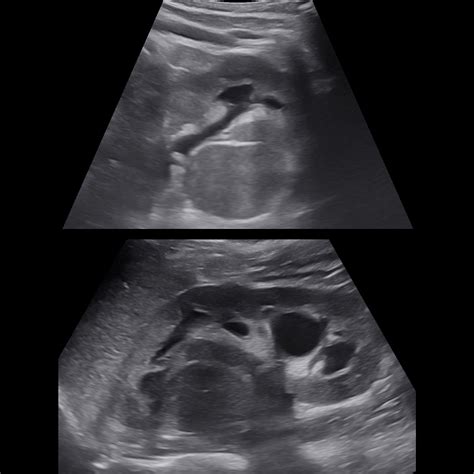

• hypertrophied column of bertin radiology

• prominent column of bertin kidney

• column of bertin ct

• hypertrophied column of bertin

• column of bertin hypertrophy

• column of bertin kidney